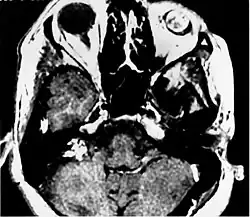

Imaging findings

Imaging studies help to identify the tumor and the specific anatomic site of involvement. Magnetic resonance images show a hyperintensity (hypervascularity) of a heterogeneous mass by T1 weighted images. Computed tomography shows a multilocular, lytic destructive temporal bone mass, centered on the vestibular aqueduct (between internal auditory canal and sigmoid sinus).[1][6][7]